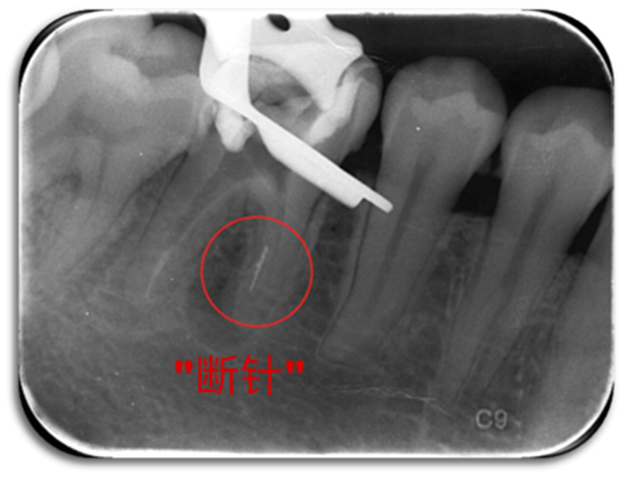

▲图源:搜狐千里眼

在根管治疗时,医生使用根管锉(钻)将牙齿根管内部的病损组织以及感染物质清除,这个过程叫做“根管预备”。此过程中,如果根管锉(钻)在根管内折断,专业术语叫做“器械分离”,这就是俗称的“断针”。

▲从根管内取出“断针”

▲我院为多位转诊患者成功取出“断针”